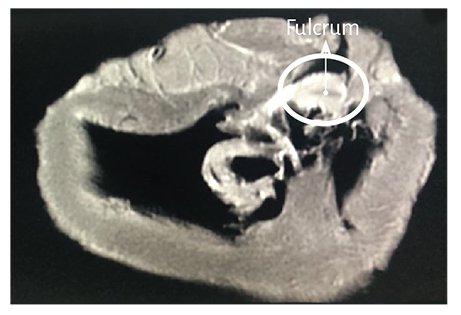

Figure 1.19. Cardiac fulcrum below the right trigone (bovine heart). The insert shows the resected piece.

The macroscopic and microscopic observation reveal the muscle fiber attachment to this solid, homogeneous nucleus, which is closely related with the aortic wall on the side of the tricuspid valve. Its configuration has been confirmed histologically. We have called his structure, origin and end of the myocardial band, cardiac fulcrum, as a parallelism and tribute to the definition of the supporting point of a lever expressed by Archimedes of Syracuse (Greek, 288 B.C. – 212 B.C.). It is located anterior to the central fibrous ridge (right trigone) and it clearly shows that the myocardial fibers of the right segment originate in its structure (Figure 1.16) same as the ascending segment courses to meet it in order to attach (Figures 1.18 and 1.19). It should be noted that to visualize the cardiac fulcrum it is essential to unfold the myocardial band. This osseous, cartilaginous or tendinous structure was always present and with the same morphology in all the hearts analyzed by us, albeit with different histological texture. No description of its characteristics or function has been reported in the literature, except the mere mention of its presence as os cordis in bovids.